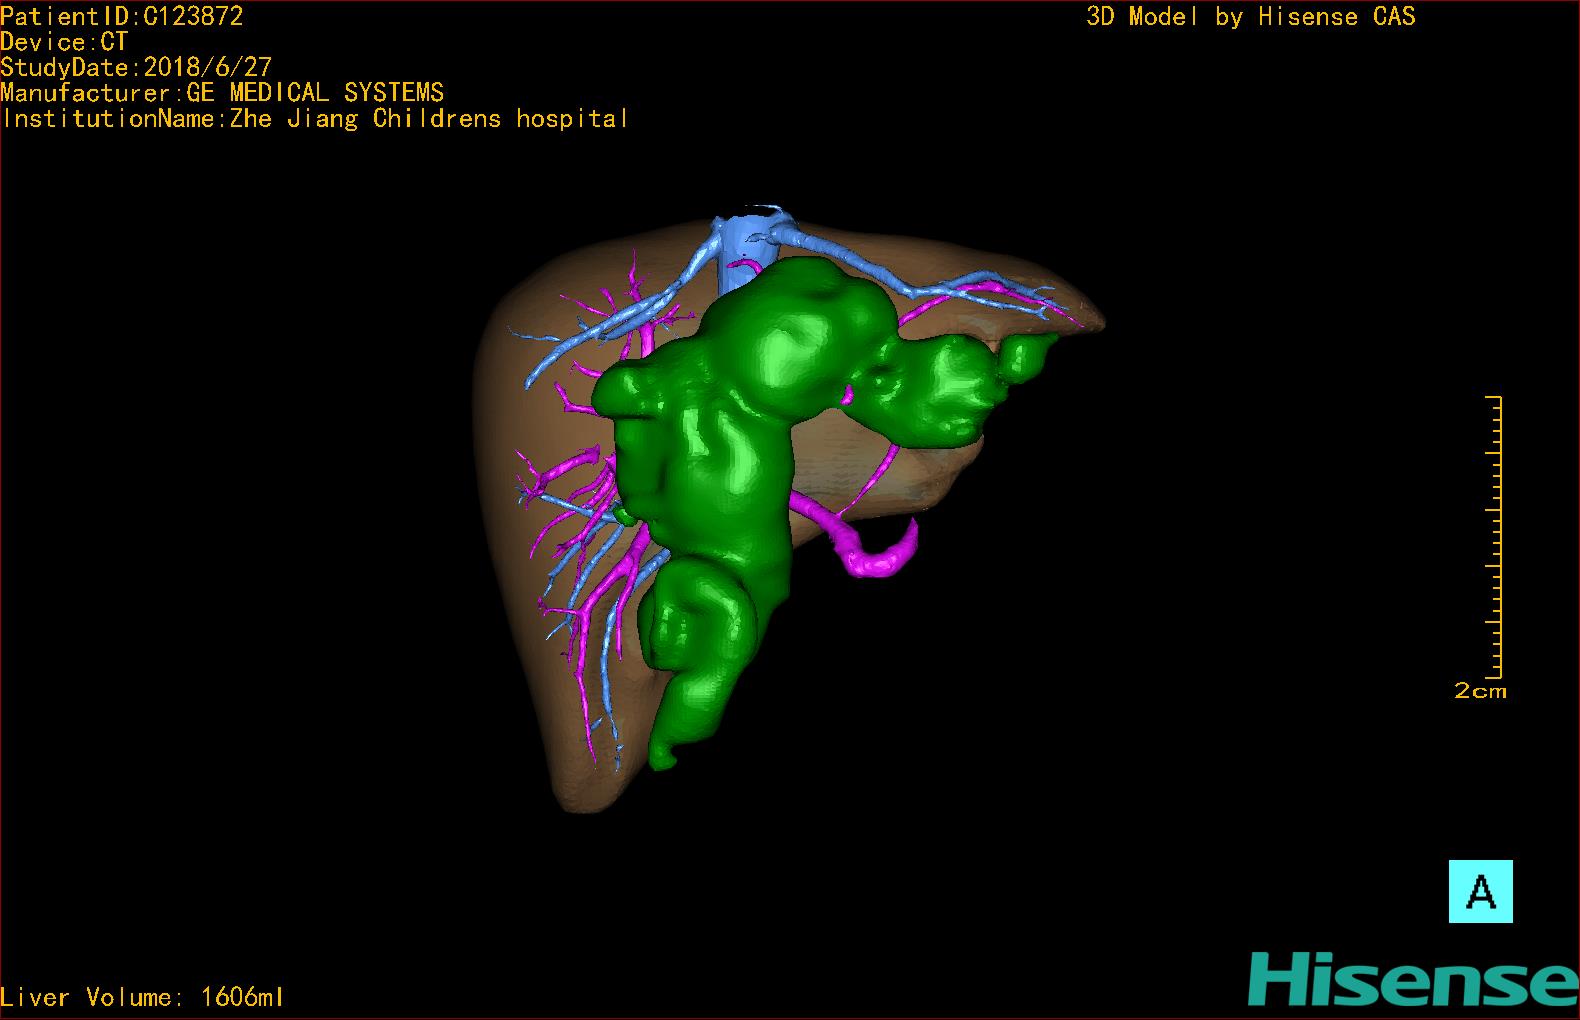

10、三维重建虚拟肝脏、胆道显像技术

三维虚拟肝脏技术是在二维影像学资料如CT等图像的基础上,通过三维重组软件和工具,比如青岛大学附属医院与海信医疗集团联合自主研发的海信计算机辅助手术系统(Hisense Computer Assisted Surgery,Hisense CAS),目前已投入临床并指导实际应用,利用该类系统对二维影像学的数据资料进行三维立体分析,重组形成立体的、有空间结构的、虚拟的肝脏三维图像。这项技术较传统的二维平面成像技术,有着明显的优势,3D虚拟肝脏技术可以构造出一个虚拟的、可视化的肝脏模型。通过对这种模型的观察,可以很容易地分辨出肝脏器官的组织结构、解剖特点,直观研究肝外胆总管的形态差异,明确肝内胆管的形态、走形、是否合并扩张、狭窄及结石,胰胆管合流的形态及共同通道内是否有狭窄、扩张和结石等病变情况,预先规划处理可能合并存在的肝内胆管扩张、狭窄或其他复杂胆道畸形,清晰地显示肝内脉管系统,包括门静脉、肝动脉及肝静脉的走行、分支,并可多角度、全方位观察病变胆道与其周围重要血管尤其是伴行的门静脉之间的解剖关系,大大提高了外科医师在术前对肝脏内部各管道结构及其变异判断的精确性和可靠性,精准地对病变进行判断和评估,还可根据患者自身的病变特点,制定出合理、个体化的手术方案,最大限度地降低术中和术后并发症发生率,并术中导航实时指导手术,提高手术的精准性和成功率。

图11:先天性胆管扩张症梭状型三维重建虚拟肝脏、胆道显像

a 图为术前二维CT扫描图像,箭头指示肝内胆管扩张;b 图为CT经多平面重组技术(MPR)所得的重建图像,可粗略地判断病变胆管的位置;c 图示术前Hisense CAS三维重建清晰显示胆管的病理形态及其与肝内三套血管系统的解剖关系;d 图示胆道系统与其伴行的门静脉系统的空间解剖关系;e 图为胆道系统立体形态,箭头处指示迷走胆管,源自肝脏直接汇入胆总管。术前规划先将迷走胆管与肝总管吻合成形,再行肝总管空肠Roux-en-Y吻合术。